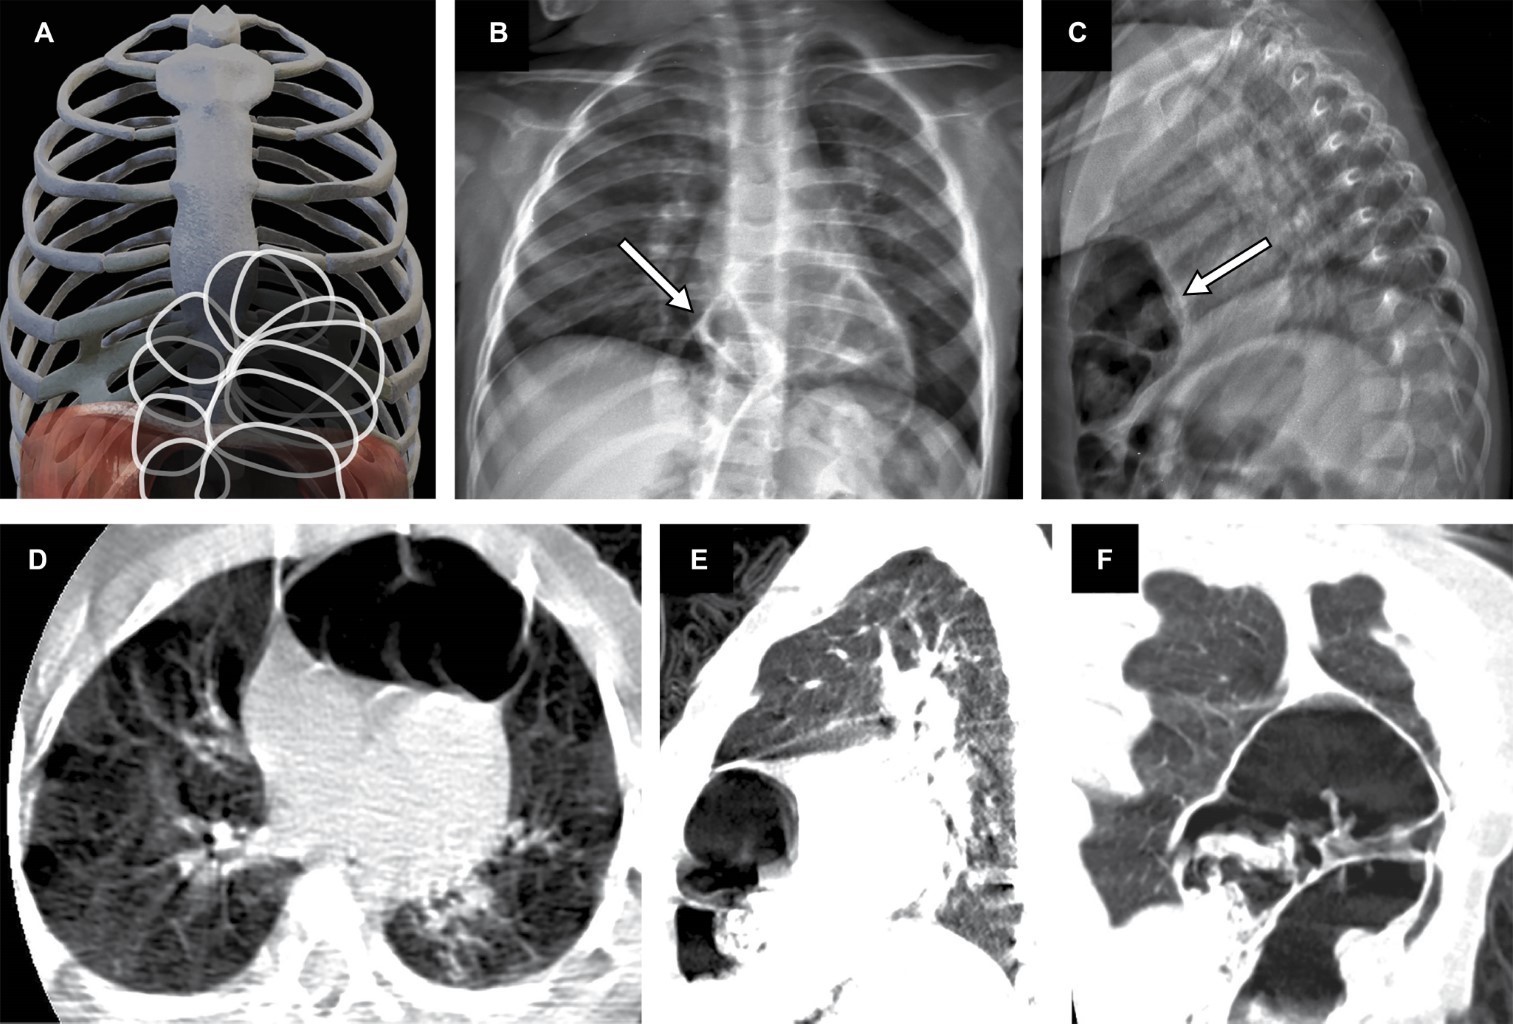

Morgagni-Larrey hernia: multimodal imaging evaluation and the importance of continuous surveillance

Morgagni-Larrey hernia, a rare congenital disability, poses challenges in its diagnosis and treatment. This article presents the case of a 24-month-old boy with a history of gastroesophageal reflux and recurrent pneumonia who presented with fever, persistent cough, and respiratory distress. Computed tomography (CT) and chest X-ray were essential in identifying an anterior diaphragmatic defect and protrusion of the transverse colon. Laparoscopic surgery, performed with the Hasson technique, allowed for precise repair of the defect with minimal invasions. The patient recovered without complications, highlighting the effectiveness of advanced imaging techniques and laparoscopy in managing this condition.

Figure 1